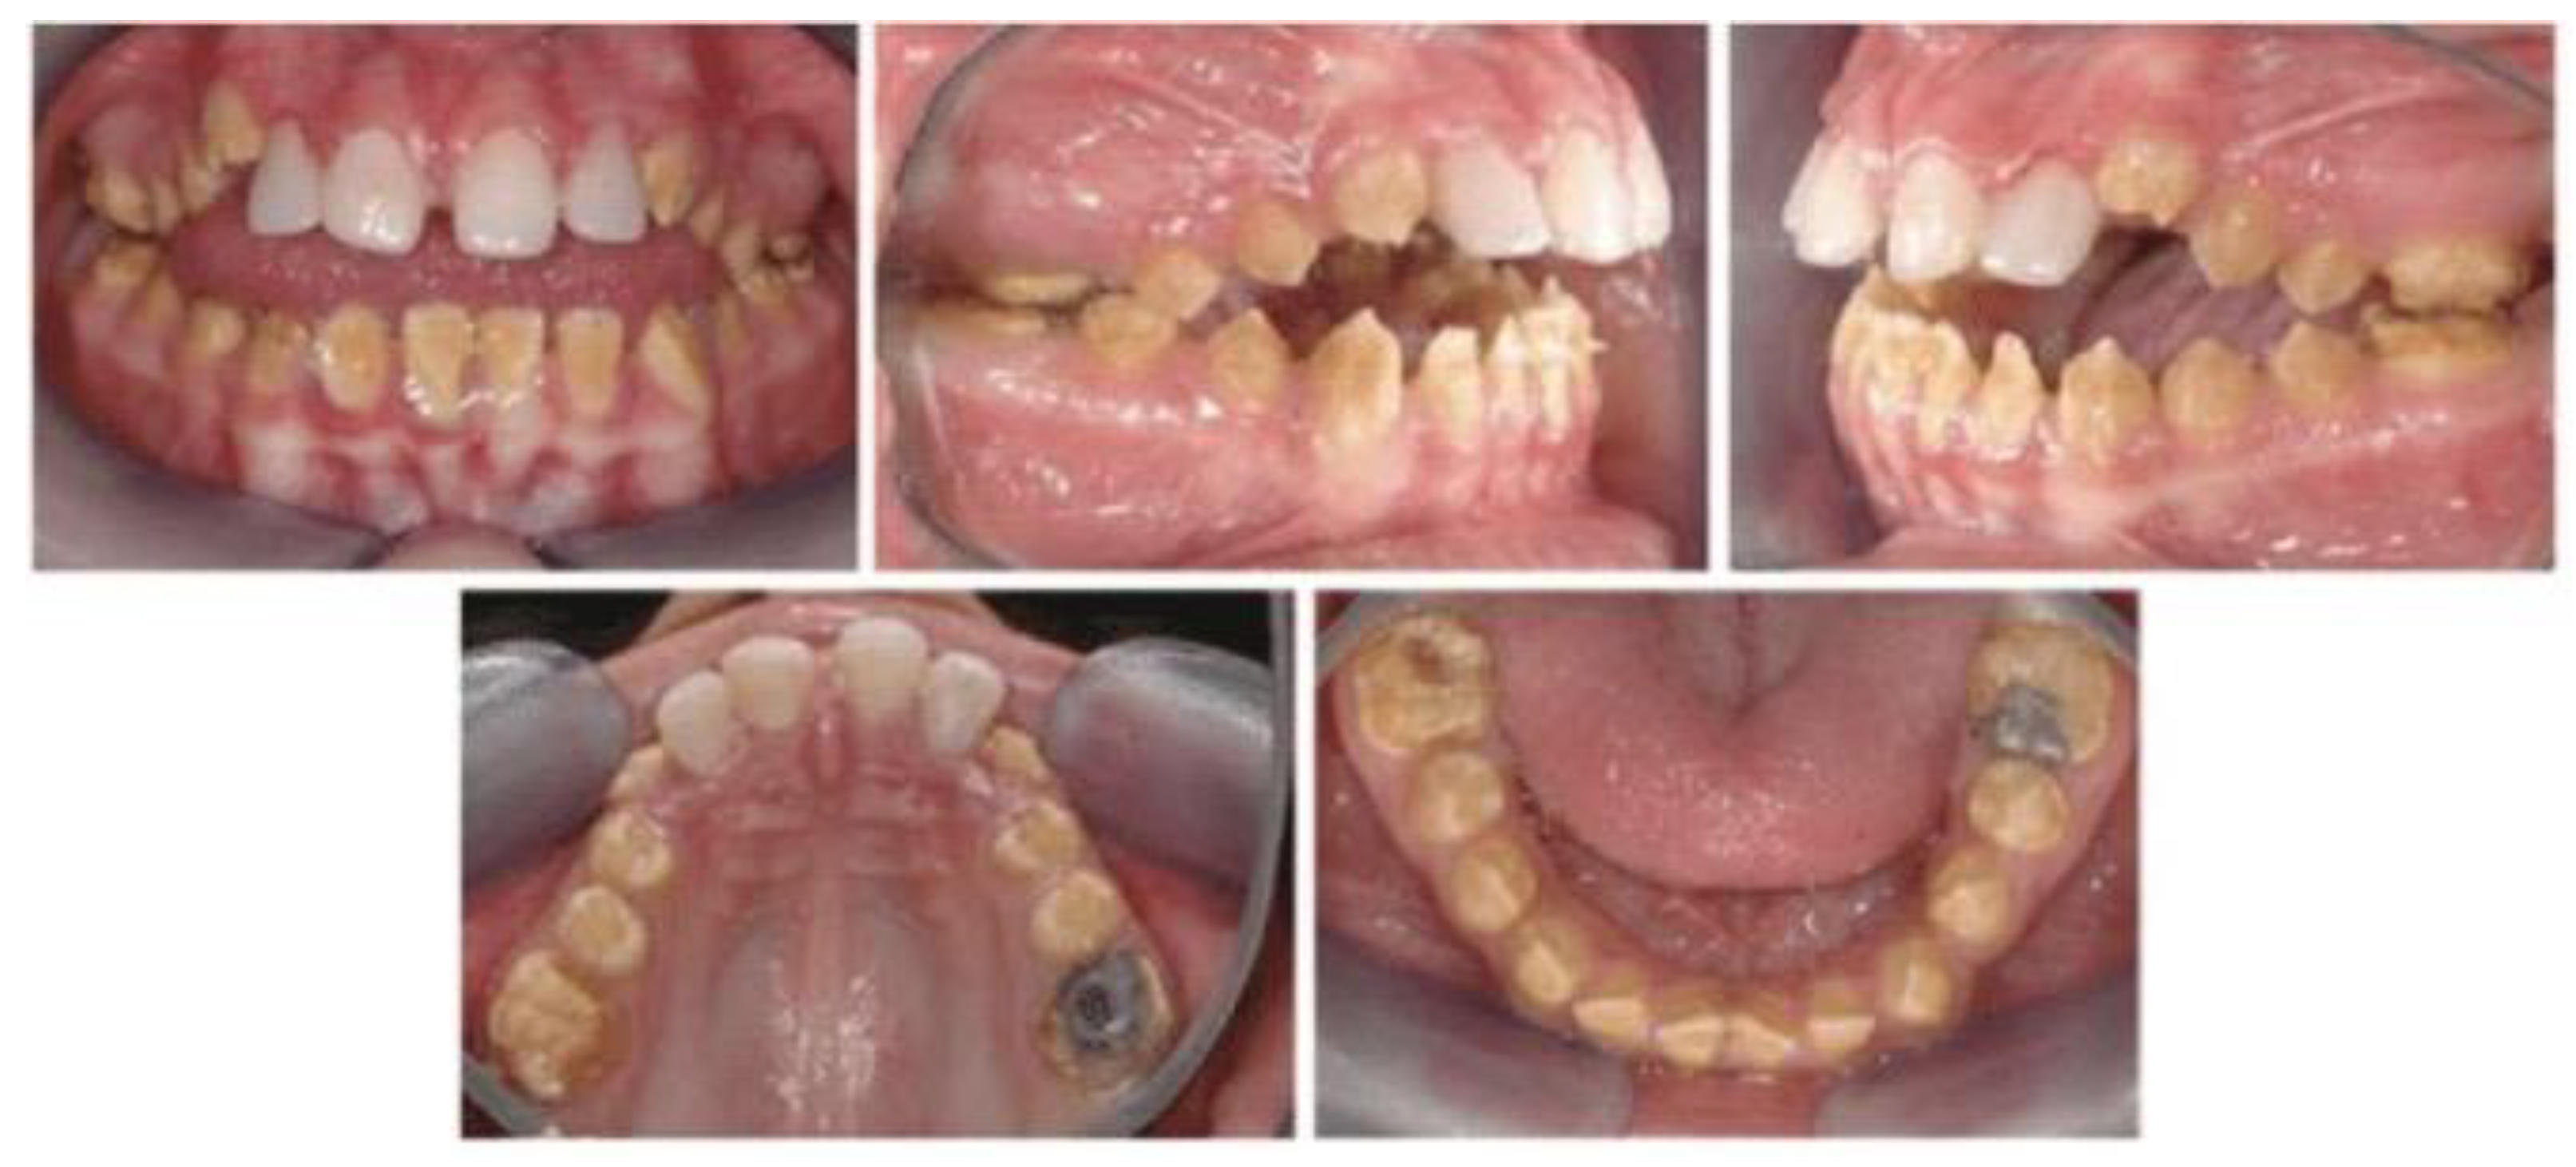

Amelogenesis imperfecta (AI) is a rare genetic disorder that affects the development and structure of tooth enamel in both primary (baby) and permanent teeth (Figure 1). It leads to unusually thin, soft, discolored, or missing enamel, resulting in fragile, sensitive, and prone to wear or breakage. AI arises from mutations in a variety of genes associated with enamel formation, including AMELX, ENAM, MMP20, KLK4, FAM83H, WDR72, and others. These mutations alter enamel matrix production, mineralization, or maturation, leading to defective enamel [20].

Individuals with AI may experience [21] discolored teeth (yellow, brown, mottled), enamel fragility, resulting in rapid wear, chipping or breakage, tooth sensitivity to temperature and physical stimuli, increased risk of cavities, inflammation, gingival problems, and malocclusions of the occlusal system, such as open anterior bite (seen in 24–60\% of cases). The diagnosis of AI is based on family history and pedigree analysis, clinical dental examination, assessment of enamel appearance and thickness, radiographs, to evaluate enamel- dentin contrast and structure. In some cases, genetic testing can confirm specific gene mutations.

Figure 1. Intraoral photos of an amelogenesis imperfecta patient, issued from [22].